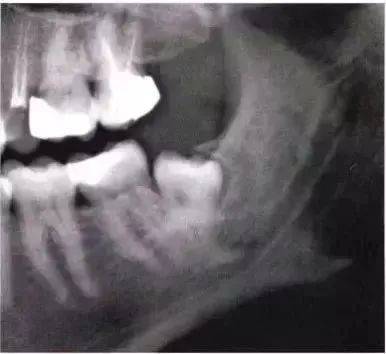

全颌曲面断层×线片。切割牙冠时应经过阻生牙远中面的牙颈部的釉牙骨质交界处。

下颌升支前缘的骨吸收区有利于牙片的取出。